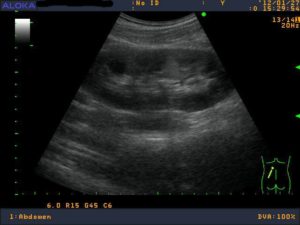

На первых этапах развития аутоиммунного сахарного диабета структура поджелудочной железы может не отличаться от нормальной. Размеры ее остаются в пределах нормы, соответствующей возрасту пациента, зернистость и эхографическая структура соответствуют физиологическим параметрам.

После пятого года болезни размер железы постепенно уменьшается, и она приобретает вид ленты. Панкреатическая ткань становится менее зернистой, ее рисунок может быть сглажен до такой степени, что становится одинаковым с клетчаткой, которая ее окружает и соседними органами.

При сахарном диабете 2 типа вначале болезни единственным признаком, который видите при УЗИ бывает незначительно увеличенная поджелудочная железа нормальной структуры. Косвенным признаком может быть отложение жира в печеночных клетках.

При длительном течении болезни проявляются следующие признаки:

- Атрофия поджелудочной железы.

- Замещение соединительной тканью – склерозирование.

- Липоматоз – разрастание жировой ткани внутри железы.

Таким образом, по УЗИ можно не увидеть сахарный диабет, но обнаружить изменения в ткани поджелудочной железы, которые помогут определить длительность болезни и составить прогноз в отношении развития осложнений диабета.